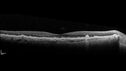

Intermediate Dry Age-Related Macular Degeneration - Soft Drusen331 views70-year-old Left eye worse than the right. Both eyes see distortion in the amsler grid for a few months

70-year-old Left eye worse than the right. Both eyes see distortion in the amsler grid for a few months

HTN, High Lipids, Osteoporosis

Meds: Lutein once daily, Calcium, Fish oil, Red Yeast Rice, CoQ10, Magnesium, MVI, Xanax

VA 20/16 OU

2+NS cataract